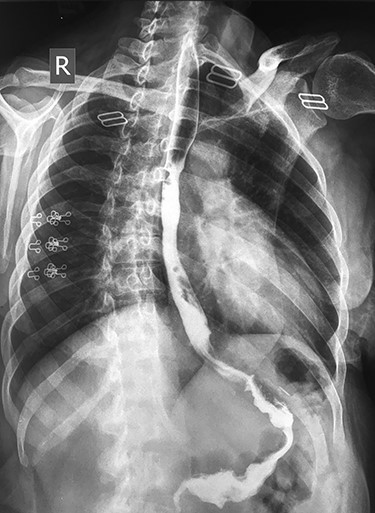

Barium study repeated after the endoscopic dilatation, which showed passage of the contrast agent to the stomach with no evidence of stricture (Fig. 3).

Barium study showing the passage of the contrast agent to the sleeved stomach with no evidence of stricture after successful endoscopic dilatation.